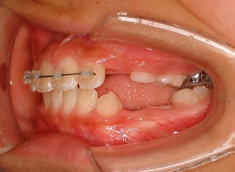

治療前

治療開始時